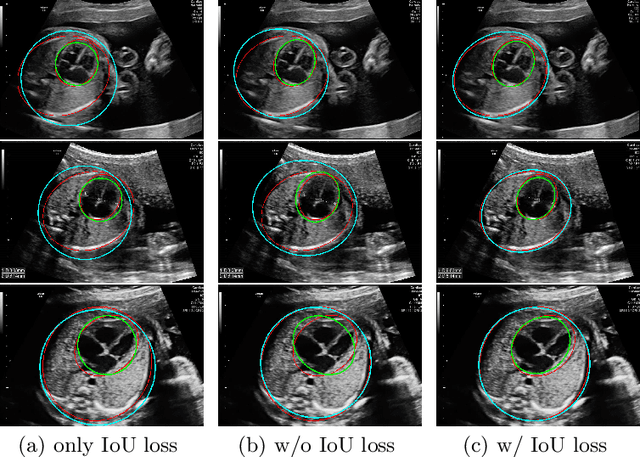

Abstract:As an important scan plane, four chamber view is routinely performed in both second trimester perinatal screening and fetal echocardiographic examinations. The biometrics in this plane including cardio-thoracic ratio (CTR) and cardiac axis are usually measured by sonographers for diagnosing congenital heart disease. However, due to the commonly existing artifacts like acoustic shadowing, the traditional manual measurements not only suffer from the low efficiency, but also with the inconsistent results depending on the operators' skills. In this paper, we present an anchor-free ellipse detection network, namely EllipseNet, which detects the cardiac and thoracic regions in ellipse and automatically calculates the CTR and cardiac axis for fetal cardiac biometrics in 4-chamber view. In particular, we formulate the network that detects the center of each object as points and regresses the ellipses' parameters simultaneously. We define an intersection-over-union loss to further regulate the regression procedure. We evaluate EllipseNet on clinical echocardiogram dataset with more than 2000 subjects. Experimental results show that the proposed framework outperforms several state-of-the-art methods. Source code will be available at https://git.openi.org.cn/capepoint/EllipseNet .